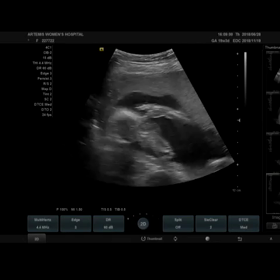

39w0d 予定日1週間前 2Dエコー 動画 育児日記